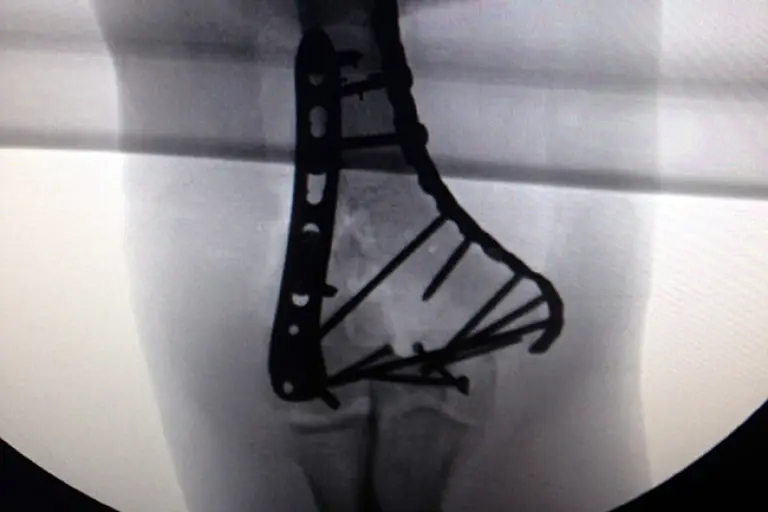

Signo de la gravedad de su lesión, Bono publicó en el sitio de internet una radiografía de su codo, luego de más de cinco horas de operación. Los médicos tuvieron que poner tres placas de titanio, fijadas con 18 tornillos.